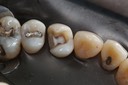

Ted Kanamori #18-19 caries removal